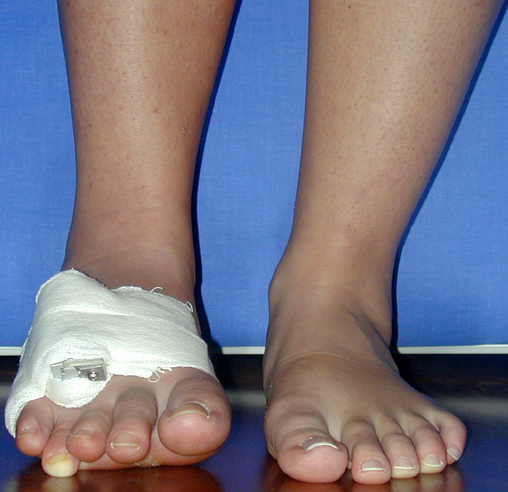

Surgical treatment may be required for metacarpal shortness because of cosmetic disturbance and fatigue in the dominant hand; and for metatarsal shortness because of cosmetic appearance, metatarsalgia, deformity due to dorsal shift of the short finger, pain and pressure ulcers due to plantar shift of the short finger, or difficulty in shoe wearing. Various techniques have been defined for the treatment of congenital metacarpal or metatarsal shortness. However, the most frequently used methods are acute lengthening with grafting, and distraction osteogenesis (callotasis). Callotasis method is preferred for lengthening more than 1 cm. In our department, we prefer distraction osteogenesis with unilateral or circular external fixator for lengthening of metacarpal and metatarsal bones.